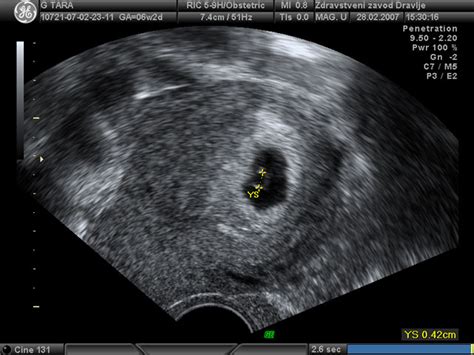

- Ultrazvok: Ultrazvočni pregled v 10. tednu lahko prikaže majhno človeško bitje. Na ultrazvočni sliki je vidna otrokova glava, ki je v tej fazi še vedno nesorazmerno velika glede na preostanek telesa. Vidni so že oblikovani zapestji in majhni prsti. Srčni utrip je močan in ga je mogoče zaznati s fetalnim monitorjem.